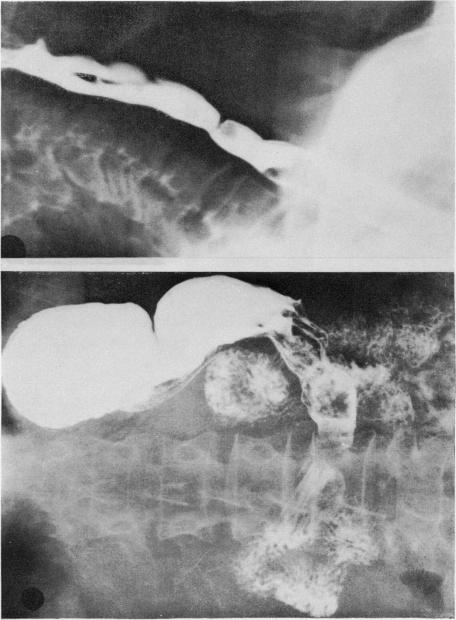

Hour-glass stricture of the stomach and iron deficiency.

Ulster Med J. 1966;35(1):50-71.